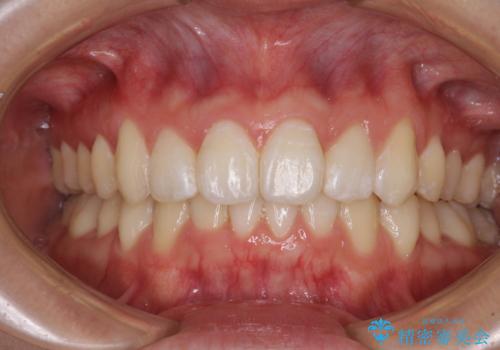

- 上下のデコボコと前歯のクロスバイトを改善したいとのことで来院された患者様です。

極力短期間で治療したいとのことで、ワイヤー装置による矯正治療を行うこととしました。

お住まいが遠方であったため、マウスピースによる矯正治療も提案しましたが、ご自身でのマウスピースの管理の面倒くささと、なるべく早く治療を終えたいとのことで、ワイヤー矯正を選択されました。